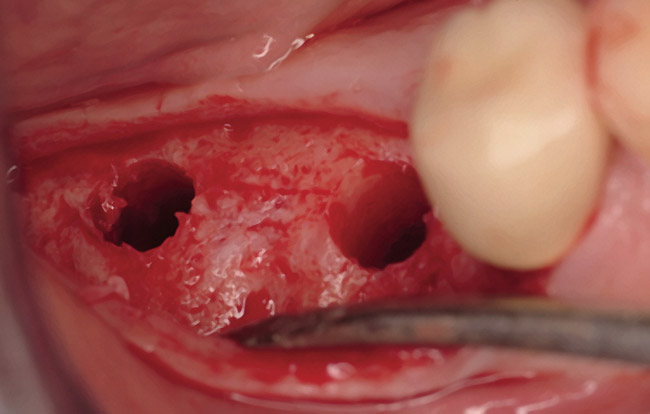

The patient was a 66-year-old man who required removal of the three mandibular right molars due to rampant caries and attachment loss. Following flap reflection and extractions, the sockets were debrided with both ultrasonic and manual instrumentation (Figure 10). The sockets of the first and second molars were augmented with rhBMP-2/ACS. The site of the third molar was obturated with a noncrosslinked, collagen plug for hemostatic purposes only.

The restorative treatment plan encompassed tooth replacement in the first and second molar positions only, negating the need for the patient to incur the greater expense of augmenting the third molar site. Primary closure was achieved with a monofilament PTFE suture. Approximately 6 months after the extractions and augmentation procedure, the patient returned for implant placement surgery. Surgical reopening revealed excellent visual regeneration and ridge preservation (Figure 11). The site of the tooth No. 31 osteotomy was chosen for biopsy harvesting, because this is where the most severe bone loss existed at the time of extraction, and this site would be most representative of new bone formation, as opposed to possibly harvesting pre-existing native bone. This trephine core qualitatively revealed what was diagnosed by the histopathologist as "normal bone" without any foreign body or inflammatory responses being evident (Figure 12). Serving as a historic control, Trombelli et al reported on histomorphometric measurements of various tissues present at different time intervals. These authors describe great variability in human trephine cores taken from extraction sites. In relation to the present case series, Trombelli et al described the presence of a provisional matrix and woven bone dominating what they described as late-phase healing taken at 12 to 24 weeks after extractions. Although tissue modeling was described as fast, the authors found the remodeling of the newly formed bone to be what they called "seemingly slow." The trephine core presented in this particular case demonstrated this type of healing, as described by Trombelli et al.8 A high degree of woven bone as well as a cell and fiber-abundant provisional matrix was present.